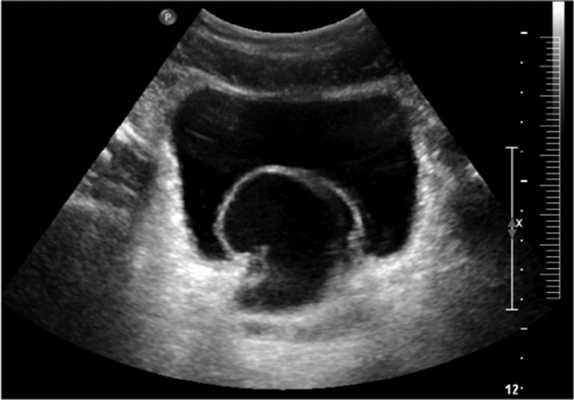

Пациент А., 32 лет, обратился в клинику урологии МГМСУ с жалобами на гипертермию до 37,0-37,3 °С в вечернее время в течение 4 мес до настоящей госпитализации, затрудненное мочеиспускание вялой струей, боли в области промежности, эпизоды острой задержки мочи, самопроизвольно разрешавшиеся. Пациент холост, детей не имеет. Из анамнеза известно, что в 16-летнем возрасте при амбулаторном ультразвуковом исследовании (УЗИ) была выявлена единственная левая почка. В последующем в другом лечебно-профилактическом учреждении при УЗИ выявлено образование мочевого пузыря (рис. 1). Рисунок 1. Трансабдоминальное УЗИ пациента А.